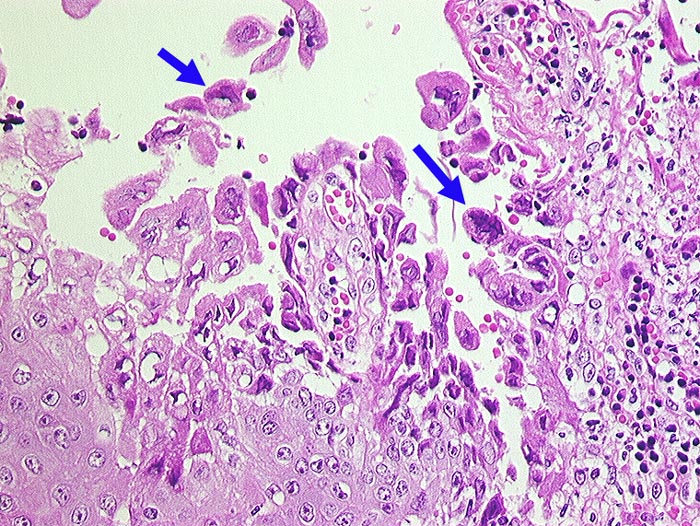

PathoPic ID 548 - Ulzeröse Herpesglossitis

Ulzeröse Herpesglossitis

Entzündung infektiös

Zunge

Ulzerierte Zungenschleimhaut. In der unmittelbaren Ulkusumgebungb teils mehrkernige Plattenepithelzellen mit Milchglaskernen.

T-Zell Lymphom mit leukämischer Ausschwemmung bekannt seit 3 Jahren. Infarktoide areaktive Pneumonie.

Histologie